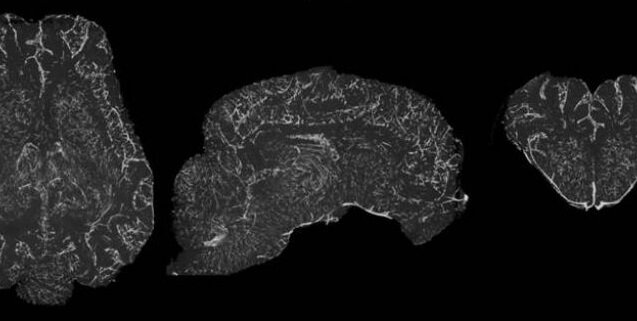

Система, которую авторы назвали BrainEx (BEx), может поддерживать циркуляцию специального перфузионного раствора в мозге, сходного по физиологическим параметрам. С помощью этого устройства перфузия может проводиться при давлении 20-140 миллиметров ртутного столба с частотой 40-180 ударов в минуту и ​​температурой 3-42 градуса Цельсия.

Система оснащена механизмами обогащения раствора кислородом и очистки токсинов. Мозг помещается в сферическую камеру, в которой поддерживается относительная влажность 95%, так что орган не высыхает, а не «купается в жидкости». Исследователи создали перфузионный раствор на основе гемоглобина без клеточных компонентов. Эхогенные вещества были добавлены к ним для облегчения испытаний. Разработанная авторами хирургическая процедура заключалась в изоляции мозга и его сосудов на уровне выше мозгового слоя.

Исследуя мозг свиньи перед подключением к системе, исследователи обнаружили, что определенные клеточные функции сохраняются. Ткани реагировали на фармакологические и иммунологические тесты, спонтанная синаптическая активность и активный метаболизм наблюдались при отсутствии мозговой активности. Исходя из этого, исследователи отметили, что способность восстанавливать функции мозга крупных млекопитающих при определенных условиях недооценивается.

В мозге, связанном с системой с перфузионным раствором BEx, сохранялась анатомическая и клеточная структура, кровеносные сосуды, обеспечивающие циркуляцию питательного раствора, нейроглифическую функцию, метаболизм тканей и электрическую активность нейронов. Исследователи обнаружили, что поведение клеток и волокон в разных частях мозга было различным.

Таким образом, в области СА1 гиппокампа, которая особенно чувствительна к недостатку кислорода, симптомы вакуолизации, повреждения мембран и цитоплазматического лизиса наблюдались даже во время теста через час после смерти. В ткани мозга, через которую пропускали контрольный раствор, наблюдалось быстрое разрушение.